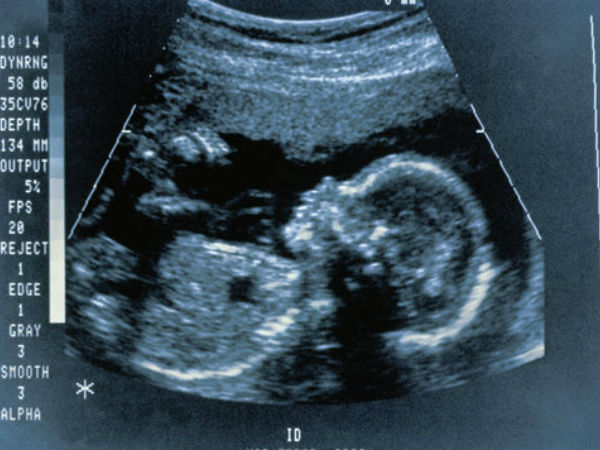

ఈ టెక్నాలజీ అందుబాటులోకి వచ్చినట్లయితే పుట్టబోయే బిడ్డకు సంబంధించి డీఎన్ఏ క్రమఅమరికలను మనకు నచ్చినట్లు చేసుకోవచ్చు.